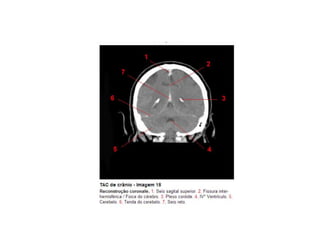

Anatomia E Protocolo Tomografia Computadorizada de Crânio PPT

Anatomia Seccional do Crâneo em Tomografia Computadorizada PPT